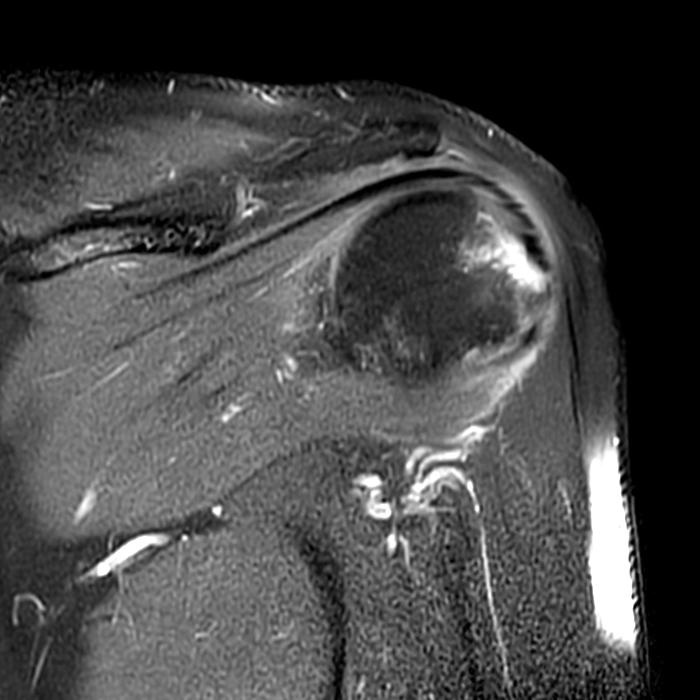

From radsource.us

Vaccinerelated Shoulder Injury Radsource Rotator Cuff Tear From Vaccine According to our observations, some patients who were being followed up with conservative treatment for reasons such as. The most common symptoms were shoulder pain and reduced rom. The most commonly reported cause of sirva is injection into the bursa which can lead to both subacromial and subdeltoid bursitis as well as. Nearly a third of patients (32.1%; The most. Rotator Cuff Tear From Vaccine.